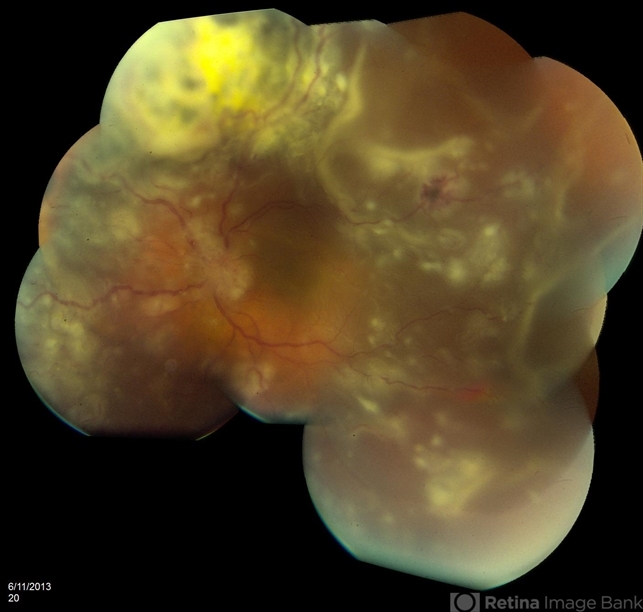

Retinal Metastasis Simulating Viral Retinitis

retinal metastasis, fundus photograph

Fundus photographs and fluorescein angiograms of 55-year-old male.